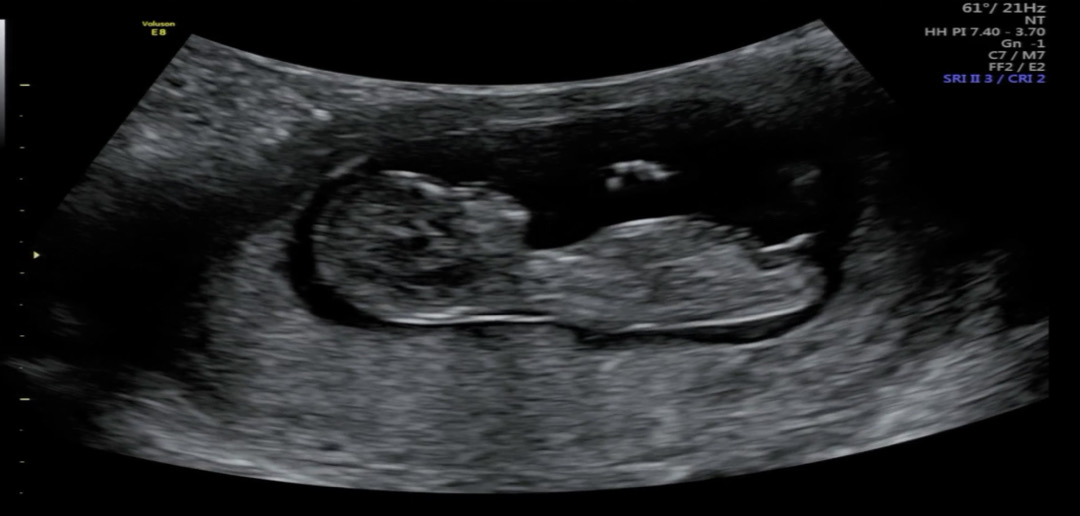

성별 봐주세용!!!

아기 성별 각도법 고수님들 투표 해주세용!!

진짜 애매하네요 딸 40프로 아들 60프로 정도로 보여요

그쵸! 엄청 애매해요ㅠㅠ 그 장꾸맘도 애매하시다고 하시더라구용...